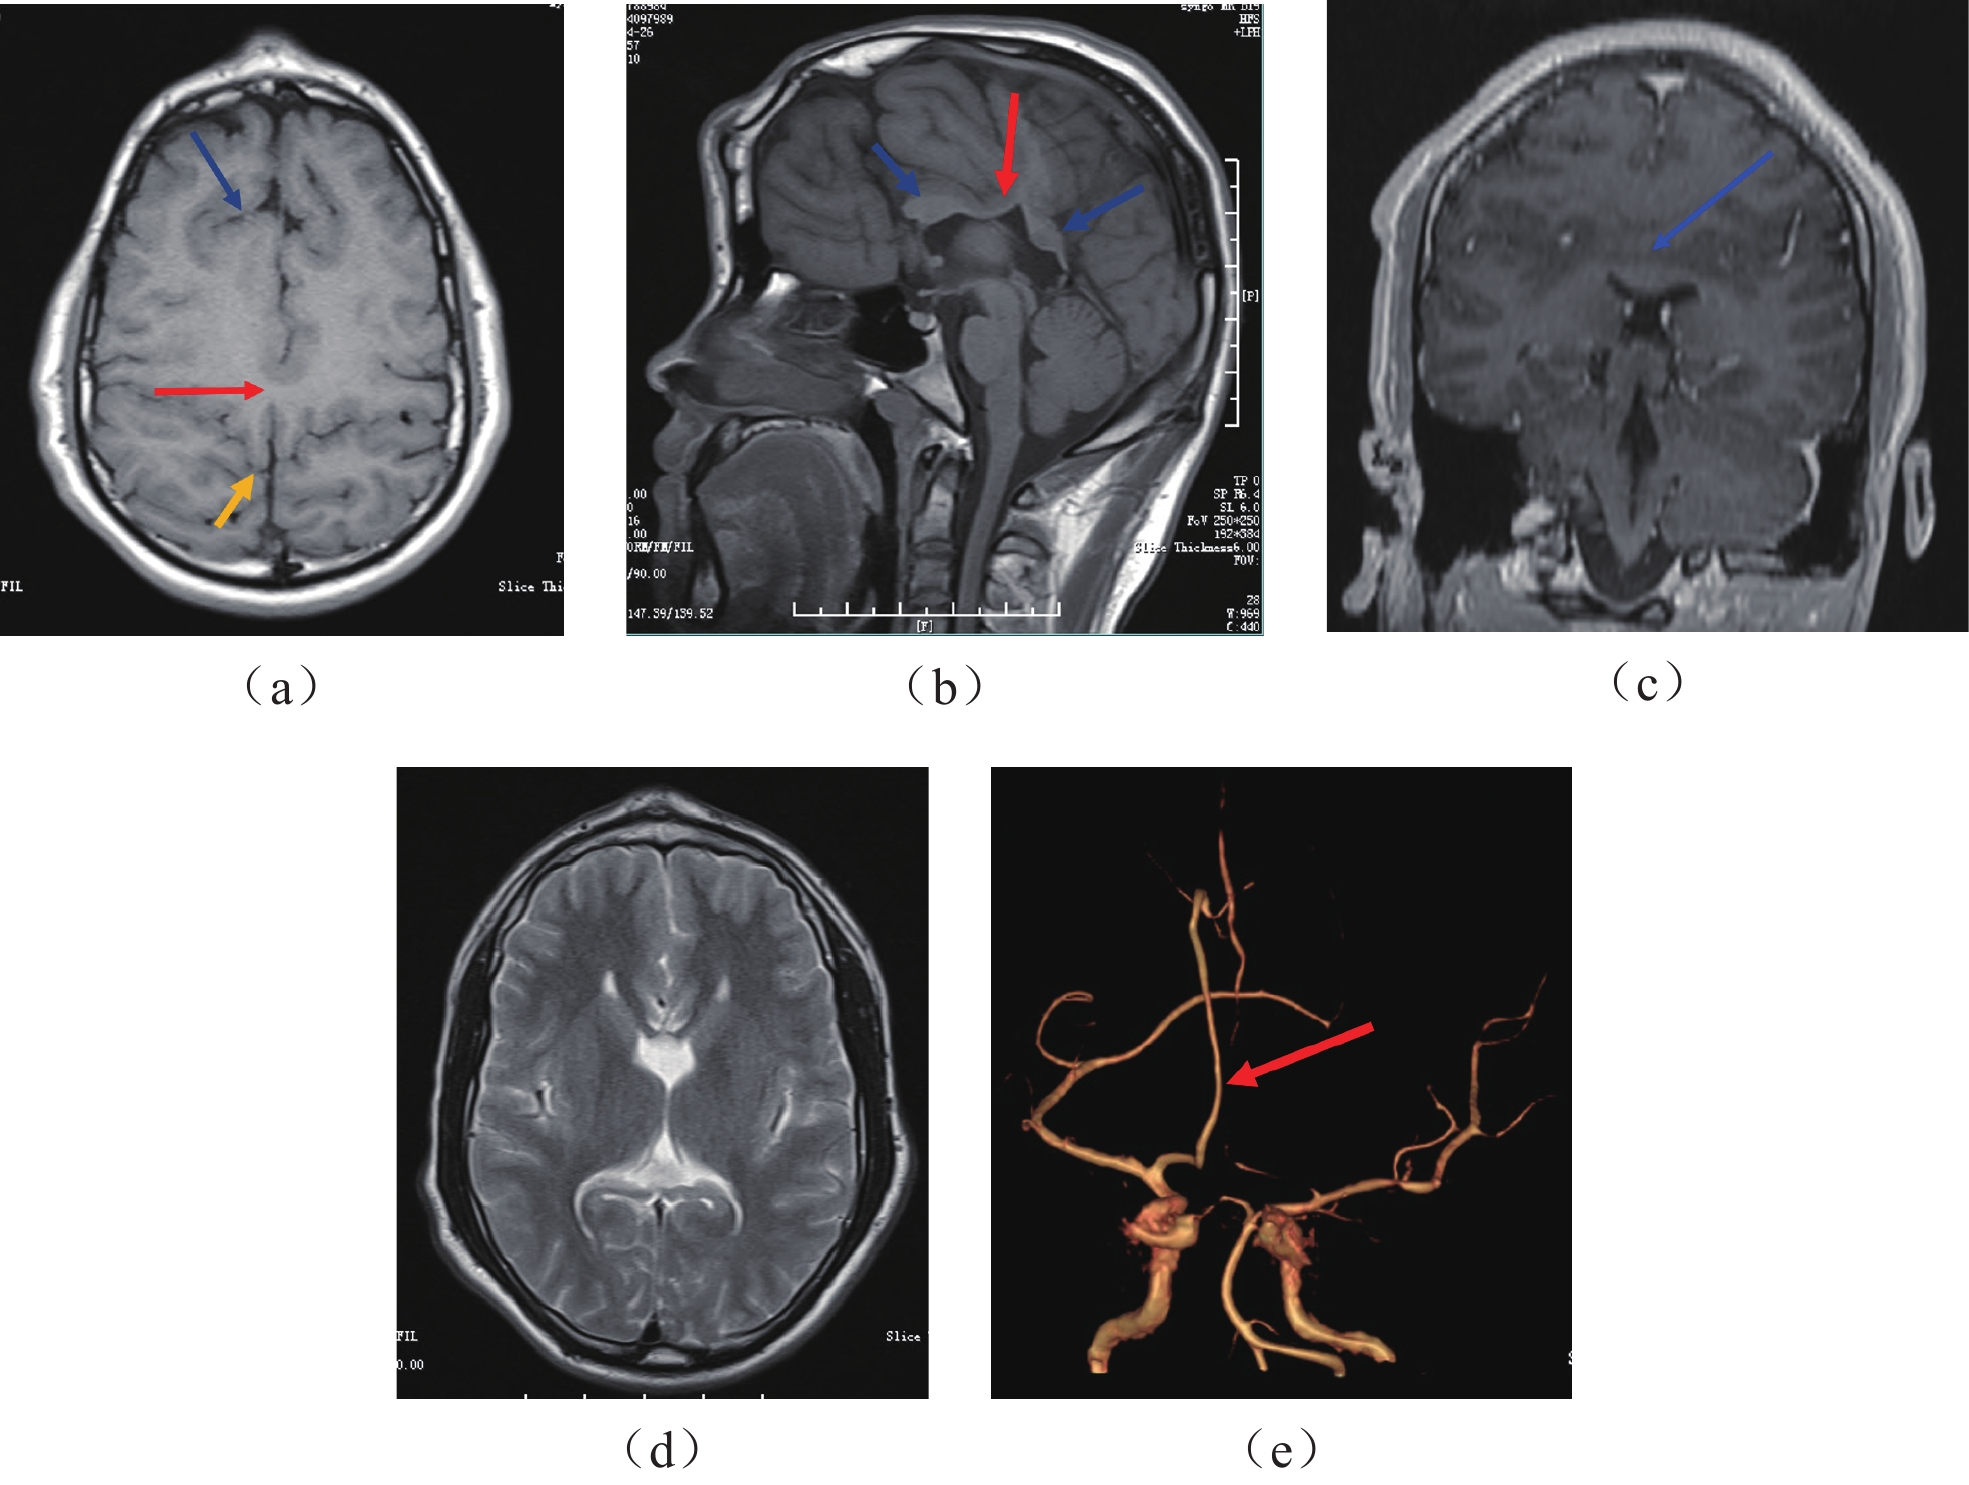

Abstract: The middle interhemispheric variant of holoprosencephaly (MIH) is a variant type of holoprosencephaly. In this article, we report the case of a 15-year-old male patient with MIH who presented with a forehead bulge immediately after birth. He was admitted to the hospital for surgery due to a frontal lesion affecting his appearance. CT and MRI revealed a frontal bone lesion and incidentally detected MIH associated with bilateral frontal lobe polymicrogyria. Postoperative pathology of the median frontal bone lesion confirmed it to be an osteoma. This article retrospectively analyzes the CT and MRI imaging features of MIH with frontal midline osteoma and reviews the literature to summarize the imaging characteristics of MIH, aiming to improve the understanding of this rare disease.